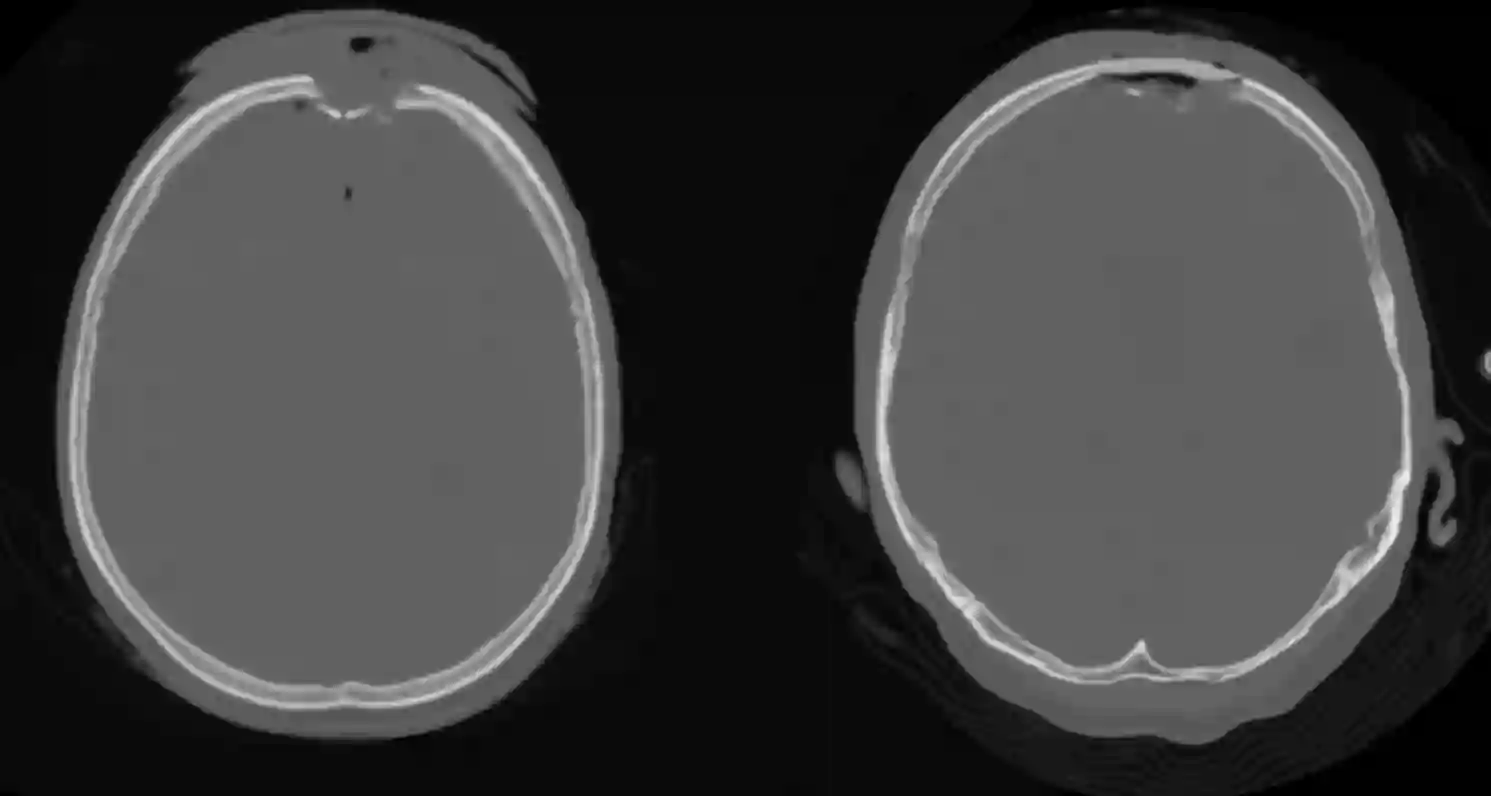

Impressionsfraktur operative Versorgung

Abbildung eines axialen CTs im Knochenfenster eines Patienten mit einer Impressionsfraktur frontal. Rechts CT Bild des gleichen Patienten nach einer notfallmäßigen Versorgung der Fraktur, welche durch eine Kraniotomie entfernt wurde und mit Palacos (Knochenzement) aufgefüllt wurde.